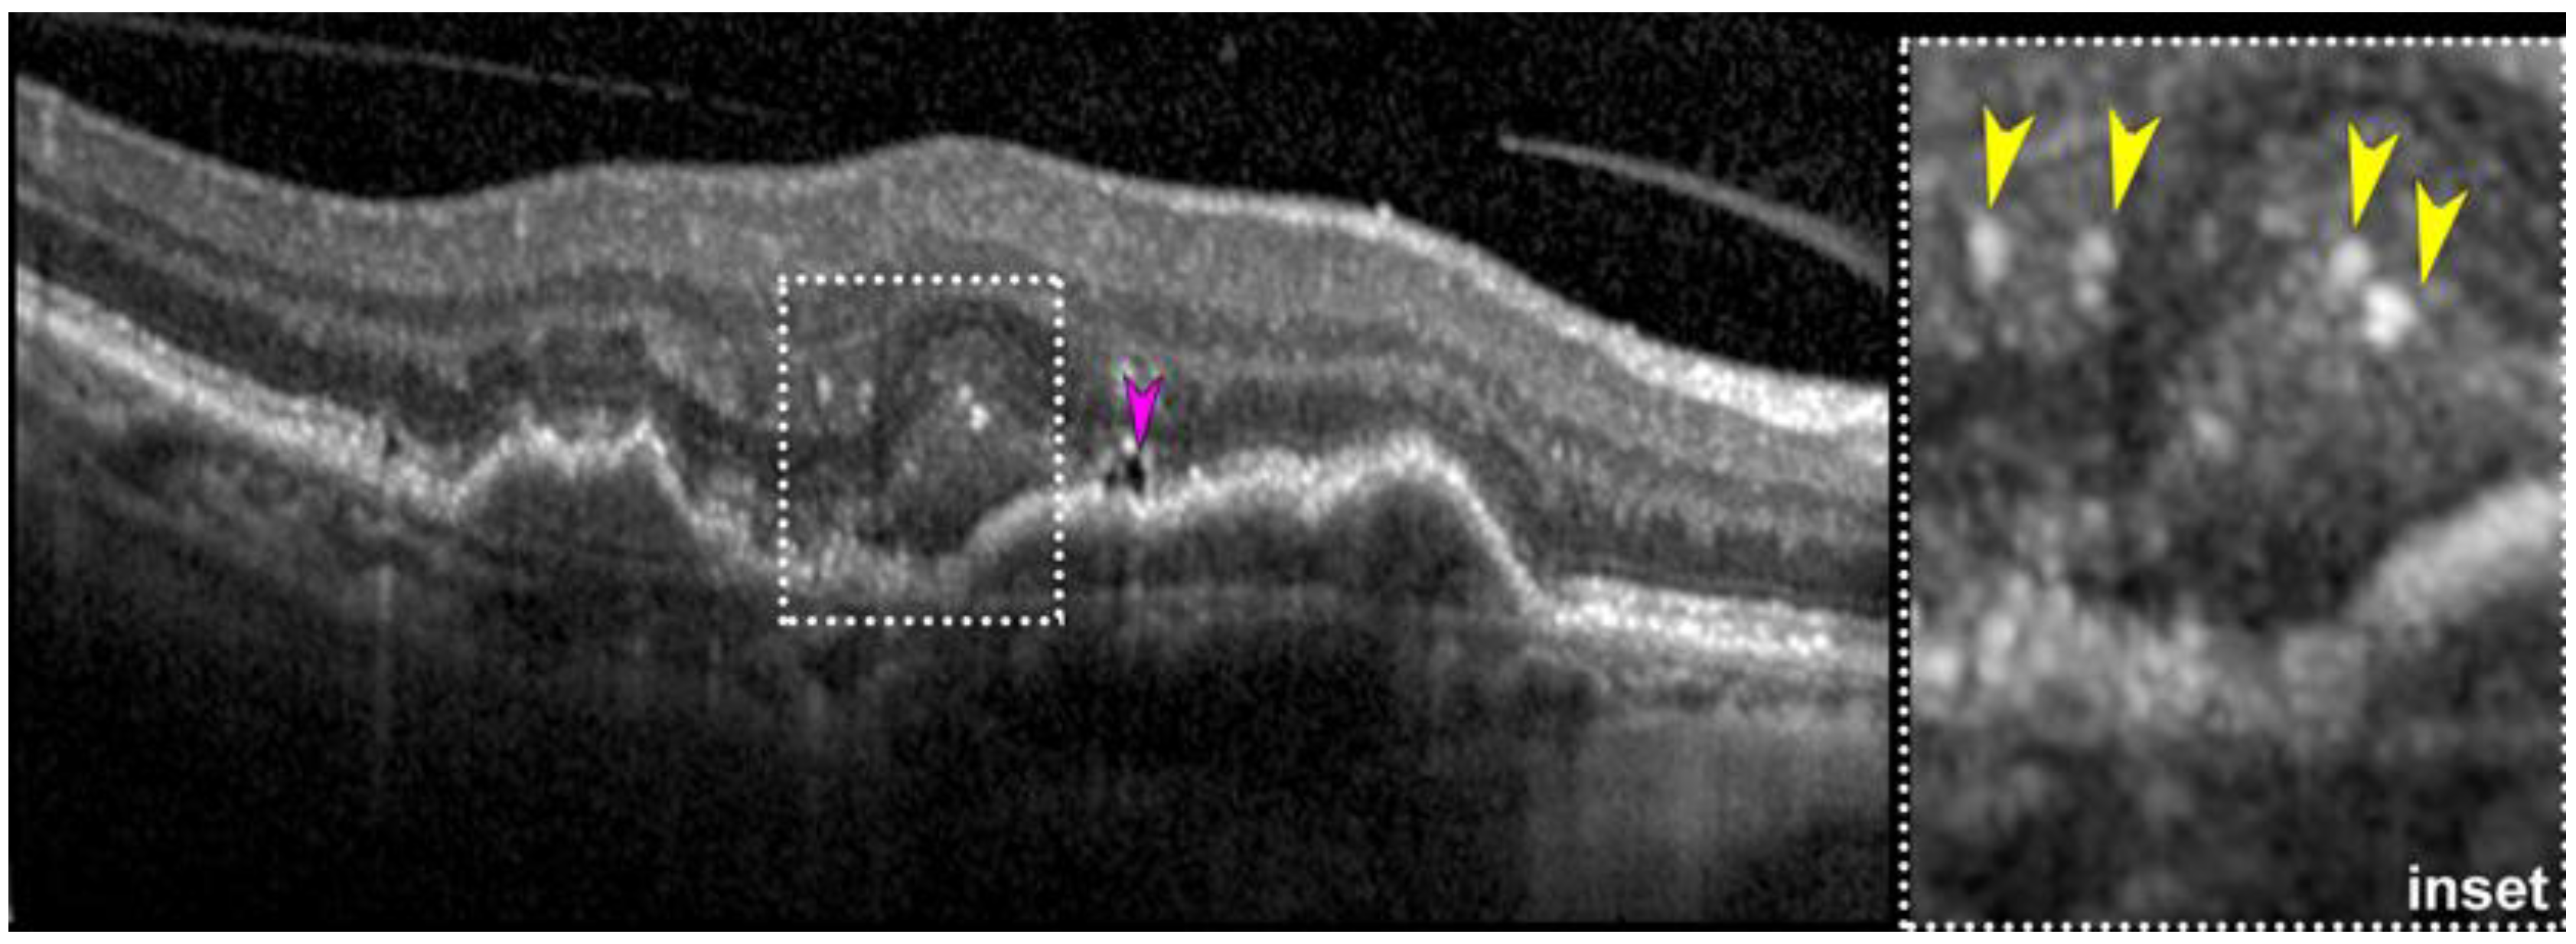

- Fragiotta, S.; Parravano, M.; Sacconi, R.; Costanzo, E.; De Geronimo, D.; Prascina, F.; Capuano, V.; Souied, E.H.; Han, I.C.; Mullins, R.; et al. Sub-retinal pigment epithelium tubules in non-neovascular age-related macular degeneration. Sci. Rep. 2022, 12, 15198. [Google Scholar] [CrossRef]

- Fragiotta, S.; Parravano, M.; Sacconi, R.; Costanzo, E.; Viggiano, P.; Prascina, F.; Capuano, V.; Souied, E.H.; Querques, G. A Common Finding in Foveal-Sparing Extensive Macular Atrophy with Pseudodrusen Implicates Basal Laminar Deposits. Retina 2022, 42, 1319–1329. [Google Scholar] [CrossRef]

- Fragiotta, S.; Dysli, C.; Parravano, M.; Sacconi, R.; Fantaguzzi, F.; Servillo, A.; Severo, A.A.; Tombolini, B.; Costanzo, E.; De Geronimo, D.; et al. Phenotypic characterization of predictors for development and progression of geographic atrophy using optical coherence tomography. Retina 2024, 44, 1232–1241. [Google Scholar] [CrossRef]

- Dolz-Marco, R.; Glover, J.P.; Gal-Or, O.; Litts, K.M.; Messinger, J.D.; Zhang, Y.; Cozzi, M.; Pellegrini, M.; Freund, K.B.; Staurenghi, G.; et al. Choroidal and Sub-Retinal Pigment Epithelium Caverns: Multimodal Imaging and Correspondence with Friedman Lipid Globules. Ophthalmology 2018, 125, 1287–1301. [Google Scholar] [CrossRef] [PubMed]

- Querques, G.; Costanzo, E.; Miere, A.; Capuano, V.; Souied, E.H. Choroidal Caverns: A Novel Optical Coherence Tomography Finding in Geographic Atrophy. Investig. Ophthalmol. Vis. Sci. 2016, 57, 2578–2582. [Google Scholar] [CrossRef]